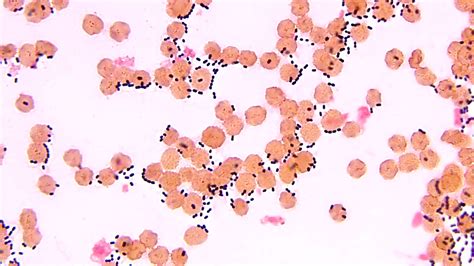

Infekcijos yra viena dažniausių kūdikių viduriavimo priežasčių. Dažniausiai jas sukelia virusai, bakterijos ar parazitai. Virusiniai susirgimai, tokie kaip rotavirusas ar norovirusas, yra labai paplitę tarp mažų vaikų ir kūdikių. Rotavirusas sukelia ypač ūmų viduriavimą kūdikiams, dažnai kartu su vėmimu, karščiavimu ir pilvo skausmu. Dėl rotaviruso gali kilti dehidratacija, todėl svarbu stebėti ir kūdikiui girdyti pakankamai skysčių. Bakterinės infekcijos, tokios kaip salmonelės, Escherichia coli (E. coli) ar Campylobacter, taip pat gali sukelti viduriavimą. Tačiau bakterijų sukeltas viduriavimas dažnai yra sunkesnis nei virusų, ir jis gali būti lydimas kraujo išmatose, stipraus pilvo skausmo bei karščiavimo. O parazitinės infekcijos yra retesnės, bet taip pat gali sukelti ilgalaikį viduriavimą.

Infekcinės kilmės viduriavimą sukeliantys virusai ir bakterijos yra labai atsparūs aplinkos poveikiui ir gali ilgą laiką išlikti ant įvairių paviršių. Jeigu iki skiepijimo vakcina roto virusas buvo viena dažniausių priežasčių viduriavimui tarp vaikų, dabar dažniausiai tokios būklės sukėlėjas - nora virusas. Pastaruoju metu Lietuvoje vaikams dažniausiai nustatomas kampilobakterijų ar salmonelių sukeltas bakterinės kilmės viduriavimas.